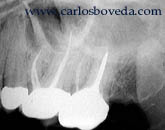

Al

llegar a nuestra consulta nos encontramos con un

paciente que refiere un dolor cada vez mayor y

predecible en este molar. Radiograficamente se

aprecia, además de otras estructuras, una

corona bien adaptada y un espacio pulpar

disminuido.